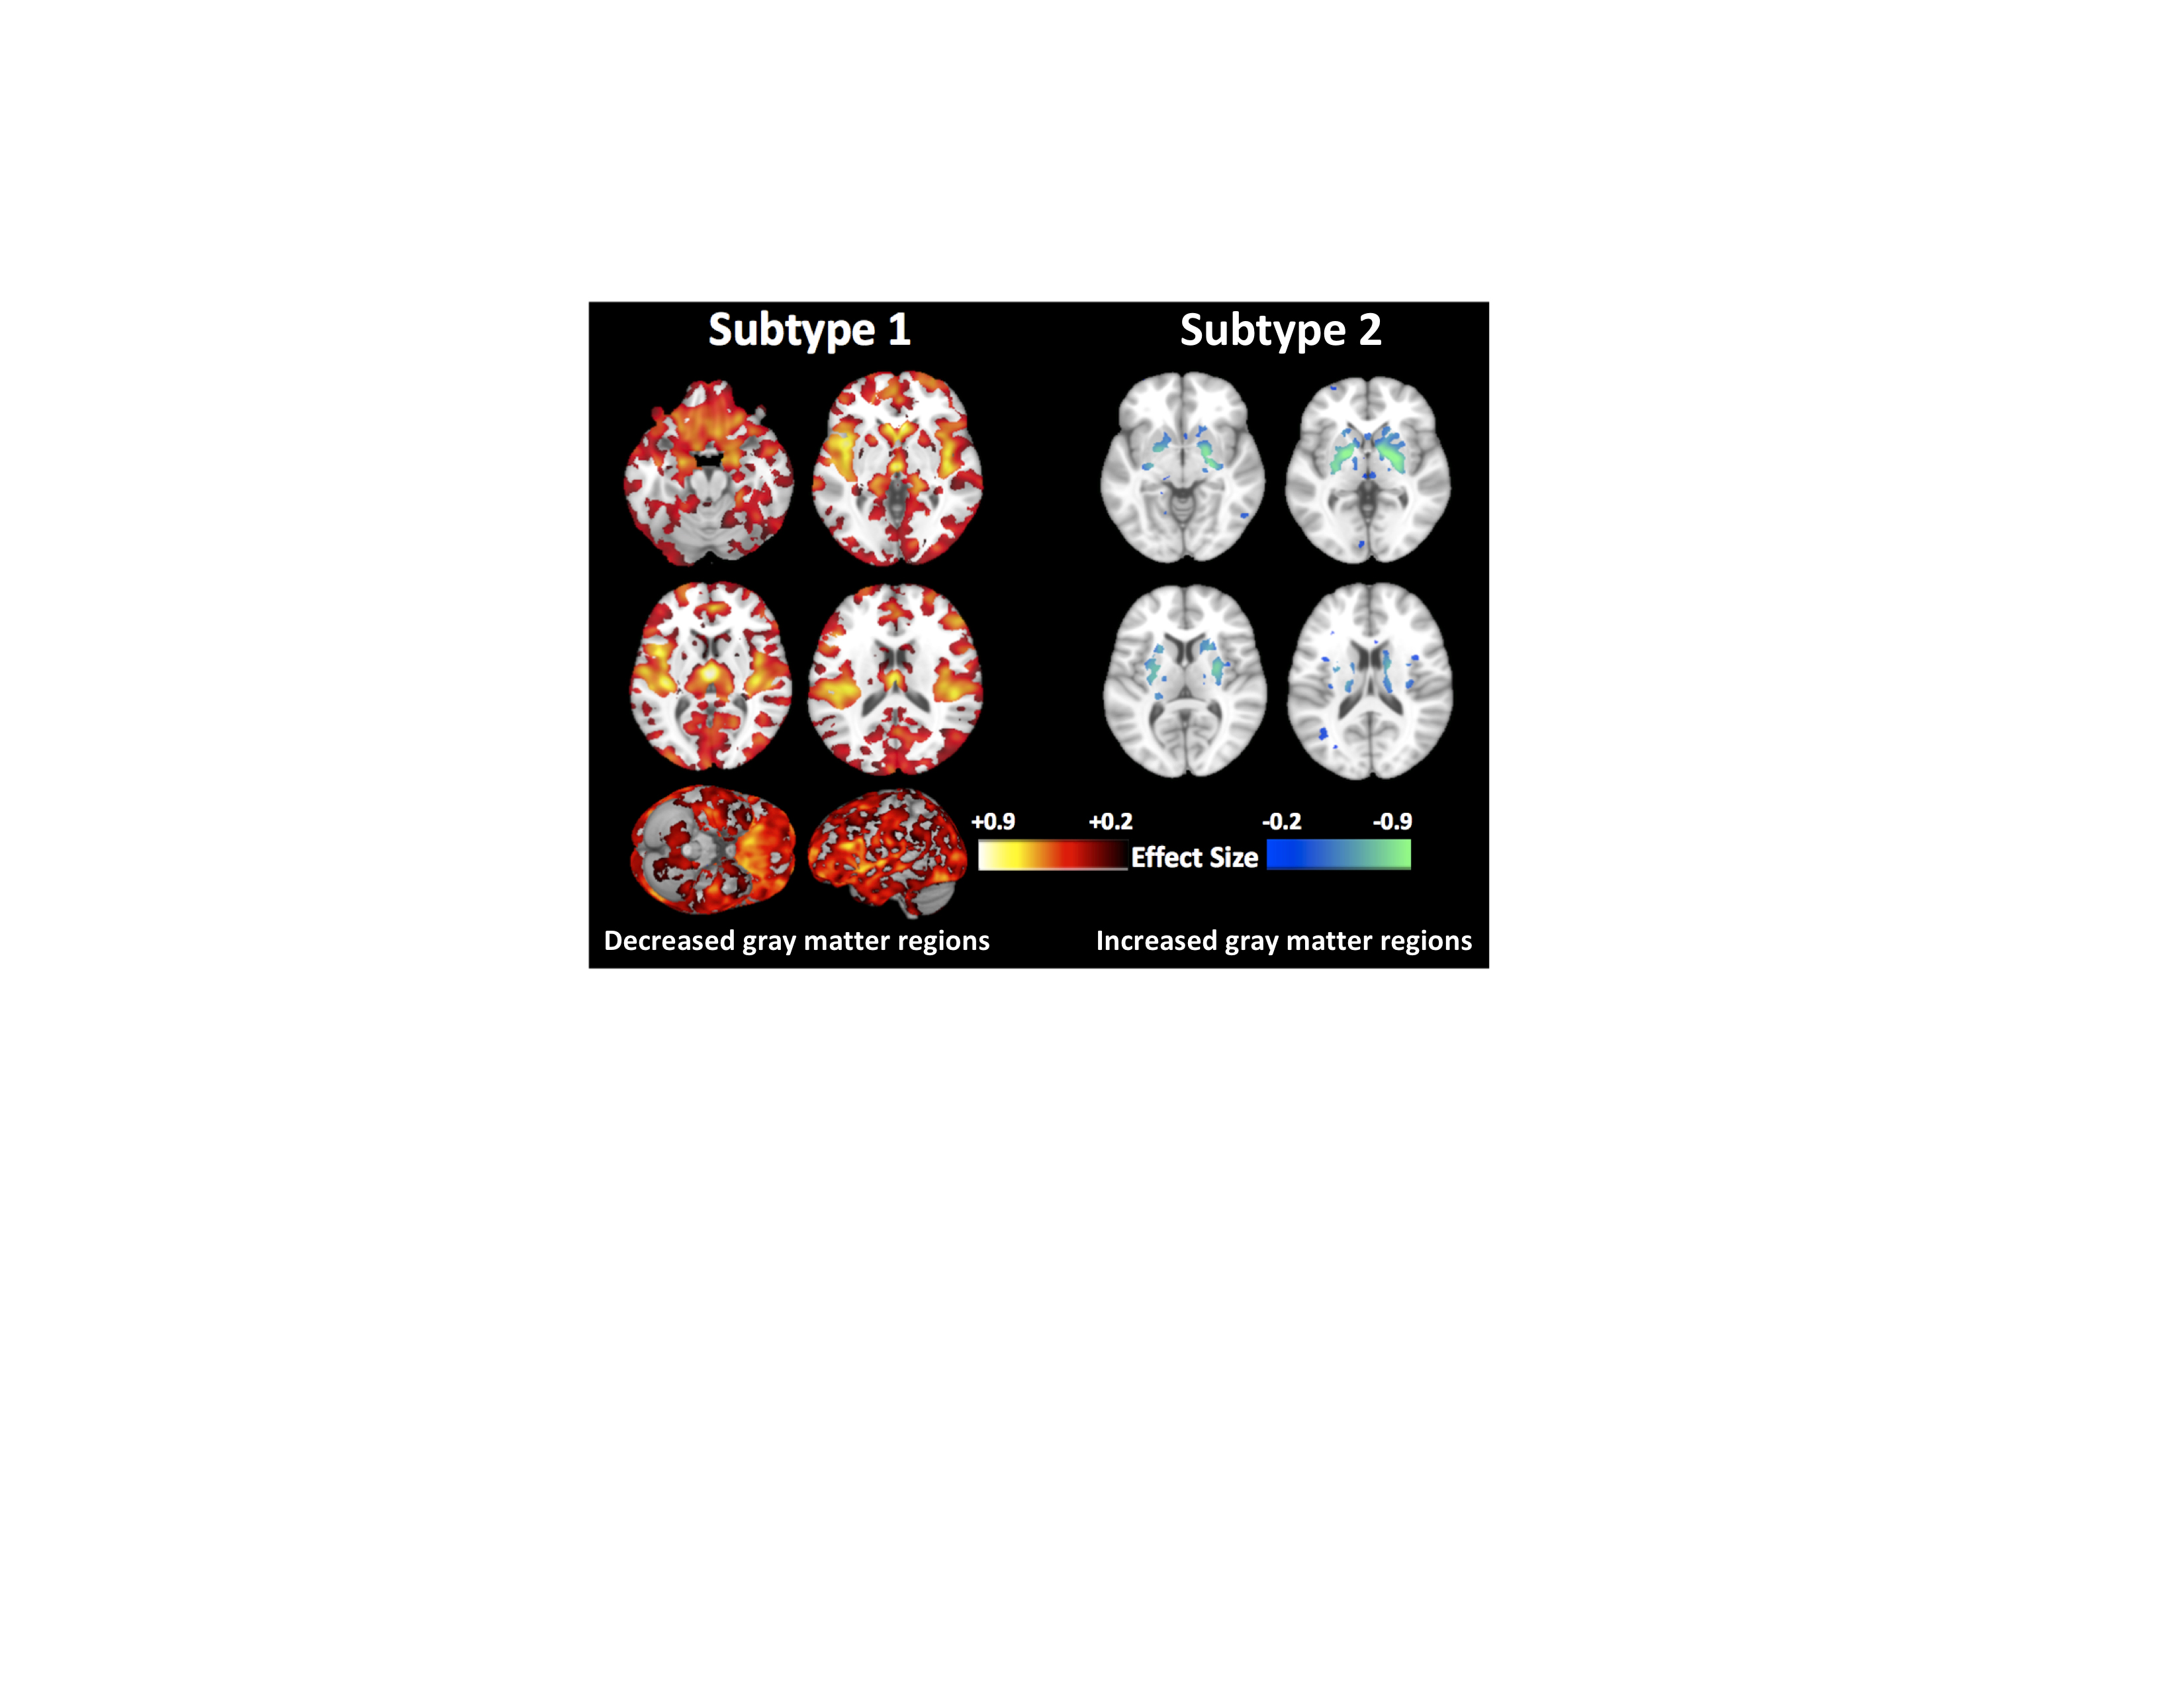

La contaminación del aire provoca daños en zonas cerebrales vinculadas al Alzheimer